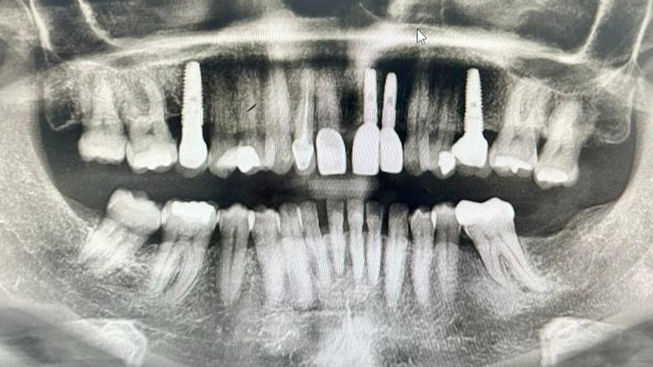

A full clinical and radiographic assessment was carried out to evaluate bone volume and soft-tissue conditions following decades of tooth loss. Treatment planning focused on a prosthetically driven implant approach, ensuring optimal implant positioning for long-term stability and aesthetics.

Two dental implants were placed in the anterior maxilla and two in posterior maxilla non guided but prosthetically driven and pre-operative smile designed.using precise three-dimensional positioning. Implant angulation, depth, and spacing were carefully planned to support the final restorations and ensure predictable outcomes.

Following successful healing, implant-supported crowns were fitted to restore the upper front teeth. Radiographic review confirmed correct implant positioning and integration.